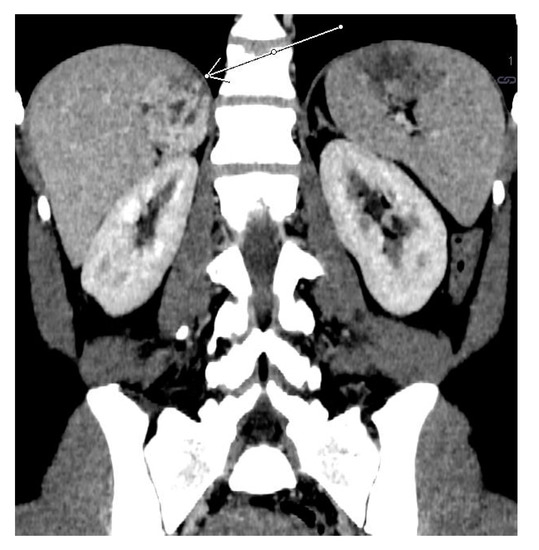

2.1. Case 1

2.2. Case 2

2.3. Case 3

2.4. Case 4

2.5. Case 5

2.6. Case 6

2.7. Case 7